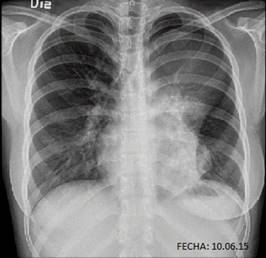

Se le tomó una radiografía de tórax donde se observó una masa homogénea en el mediastino anterior y proyectado sobre el tercio superior del hemitórax izquierdo, de contornos bien definidos, que mide aproximadamente 101 × 93 mm. La silueta cardiaca fue normal (figura 1).